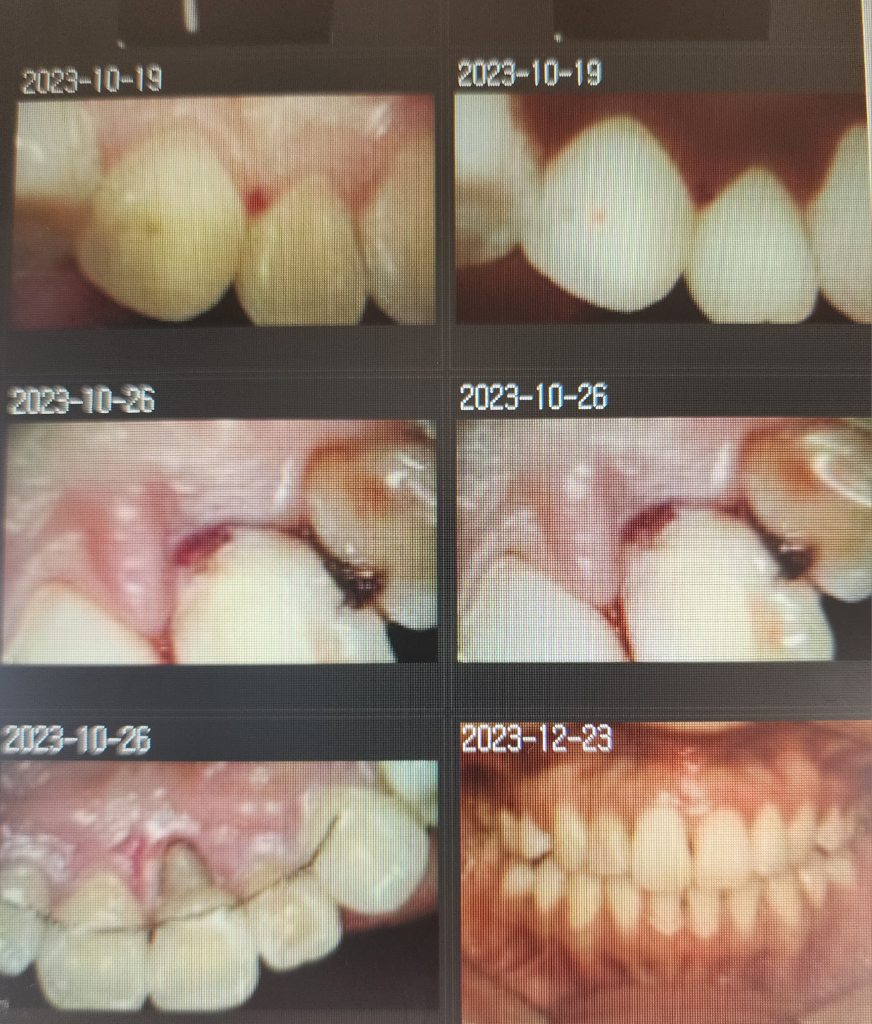

그래서 신경치료했던것을 다 긁어낸 후 다시 신경치료하고 그 이후 실활치미백을 진행했고, 9월-10월 사이 3번의 미백치료로 밝아진 줄 알았으나 12월쯤 다시 어두워지기 시작해 한번 더 받아 총 4번의 미백을 진행했습니다.

타임라인은 아래와 같습니다.

2회차 미백치료 진행시에 잇몸부분과 거의 맞닿아 있는 부분만 아직도 까맣게 되어있었고 치아 내부를 조금더 파낸 뒤 3회차 미백을 진행했습니다.

그리고 교정유지장치를 다시 달기 전 스케일링을 부탁드렸고 스케일링을 받고 나니 충치로 인해 치아가 부서져있는것을 발견하게 되었습니다.

그래서 충치치료를 진행한 것이 이 두 사진입니다.

이 두사진은 레진으로 덮기 전 상담받는 당시 사진입니다.